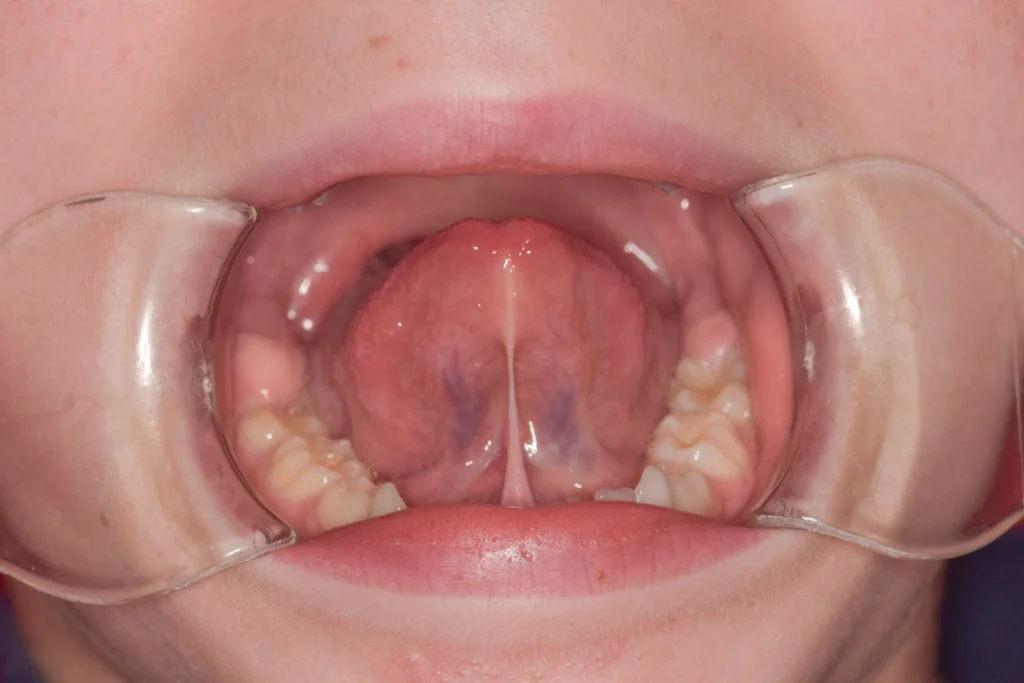

Una definición correcta es decir que, el frenillo lingual es un pliegue de mucosa que se extiende desde la cara inferior de la lengua hasta el suelo de la boca. Su función principal es ayudar a estabilizar la lengua, permitiendo a la vez un movimiento adecuado para hablar, masticar, tragar y succionar.

Dentro de la boca existen otros frenillos (por ejemplo, el frenillo labial superior o el inferior), pero el frenillo lingual es el que más relación tiene con la función de la lengua. Por eso, cuando hablamos de “frenillo en la boca” como causa de problemas de lactancia o de pronunciación, casi siempre nos referimos al frenillo lingual.

Hablamos de frenillo lingual normal cuando la lengua puede moverse con libertad en todas las direcciones: se puede sacar más allá del borde de los labios, tocar el paladar, mover de un lado a otro y ayudar en una deglución y una masticación correctas. Aunque el frenillo pueda verse más o menos marcado, lo importante no es el aspecto, sino que no limite la función.

El frenillo lingual corto, también llamado anquiloglosia, aparece cuando esa banda de tejido es demasiado corta, gruesa o se inserta muy cerca de la punta de la lengua. En estos casos, la lengua no puede elevarse ni proyectarse hacia delante con normalidad.

Desde un punto de vista práctico, cuando hablamos de frenillo lingual normal vs corto nos fijamos sobre todo en la movilidad y la función de la lengua y no tanto en la apariencia. Si la limitación funcional es clara y genera síntomas, podemos valorar la necesidad de tratamiento.